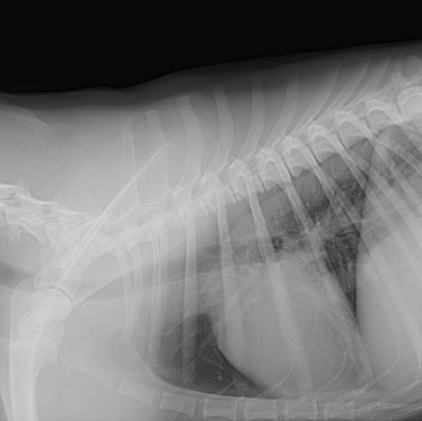

Radiography is a valuable diagnostic tool in veterinary medicine. As we continually strive to offer the highest quality medicine and diagnostic testing, we are pleased to offer radiology services as a means of providing excellent care to our patients.A radiograph (sometimes called an x-ray) is a type of photograph that can look inside the body and reveal information that may not be discernable from the outside. Radiography can be used to evaluate almost any organ in the body, including the heart, lungs, and abdominal organs, as well as the bones.

Radiography is painless, safe, and completely non-invasive, and it uses only very low doses of radiation. Because the level of radiation exposure needed to perform radiography is very low, even pregnant females and very young pets can undergo radiography. Radiographs can be used to evaluate bones as well as the size, shape, and position of many of the bodys organs. The size of organs is important because some medical conditions such as kidney, heart, or liver disease can alter the size of these organs. The shape and position of organs can be altered or distorted by certain medical conditions, including intestinal blockage or cancer. Tumors, depending on their size and location, can also sometimes be detected using radiography. Radiography can also be used to diagnose bladder stones, broken bones, chronic arthritis, certain spinal cord diseases, and a variety of other conditions.